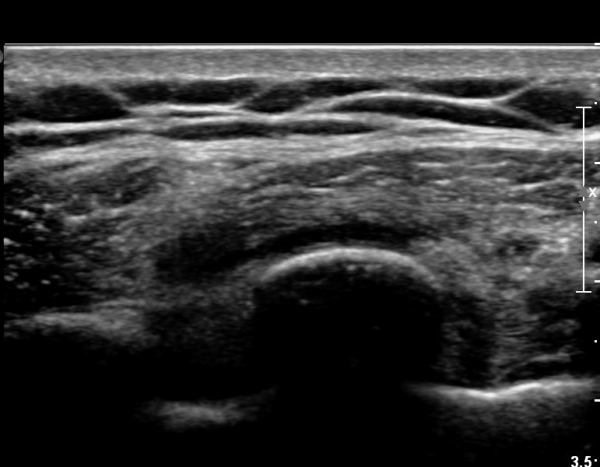

8¹øÂ° °¥ºñ»À Á¾´Ü¸é°Ë»ç»ó °¥ºñ»À Ç¥ÃþÀ¸·Î Àú¿¡ÄÚ ºÎÁ¾°ú °¥ºñ»À Ç¥Ãþ¿¡ ÀÖ´Â

±Ù¼¶À¯µéÀÌ Ç¥ÃþÀ¸·Î ¹Ð·ÁÀÖ´Â °ÍÀÌ °üÂûµÇ°í(»çÁø 1, 2)  °¥ºñ»À ÇÇÁú°ñ ¿¬¼Ó¼º

´ÜÀýÀÌ ÀǽɵȴÙ(»çÁø 2).